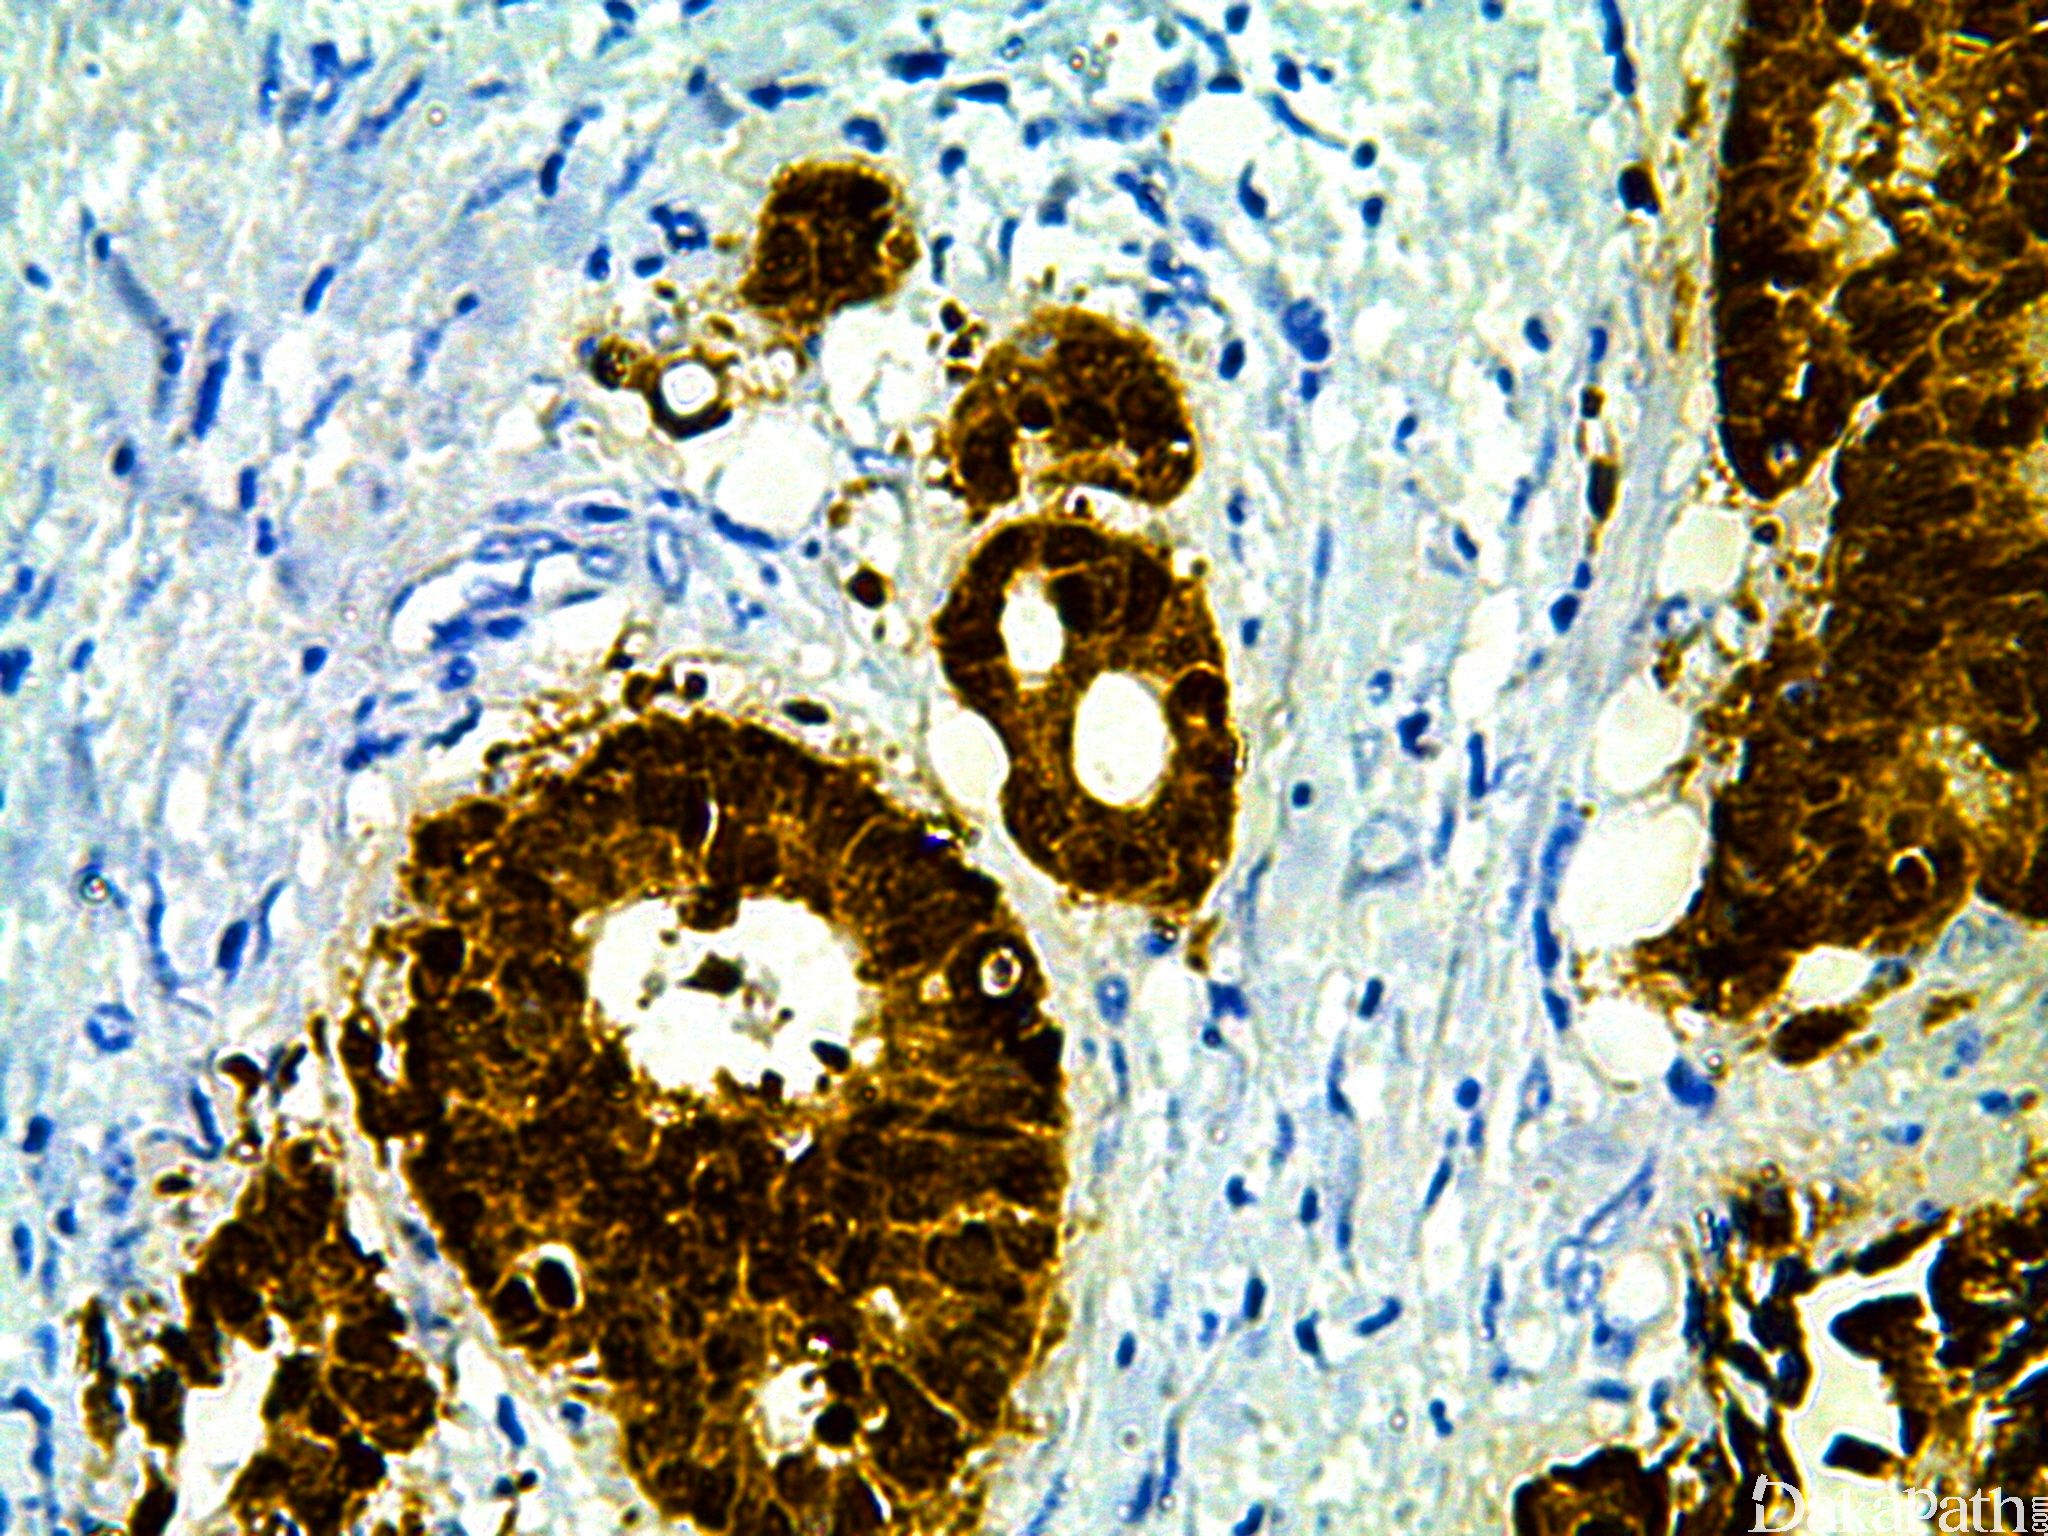

CDX-2

别名: 尾型同源盒基因转录因子-2

肠特异性转录因子,尾型同源盒基因家族的一员,调节肠上皮细胞的增殖和分化。目前认为它可能是一种肿瘤抑制基因,通过选择抑制同源盒基因转录,诱导肠上皮黏膜癌变。几乎所有大肠 和小肠肿瘤均阳性。其它器官伴有肠型上皮分化的肿瘤均可阳性,如膀胱、胃、食道、肺和卵巢黏液性肿瘤均可高表达。

信号定位: 胞核